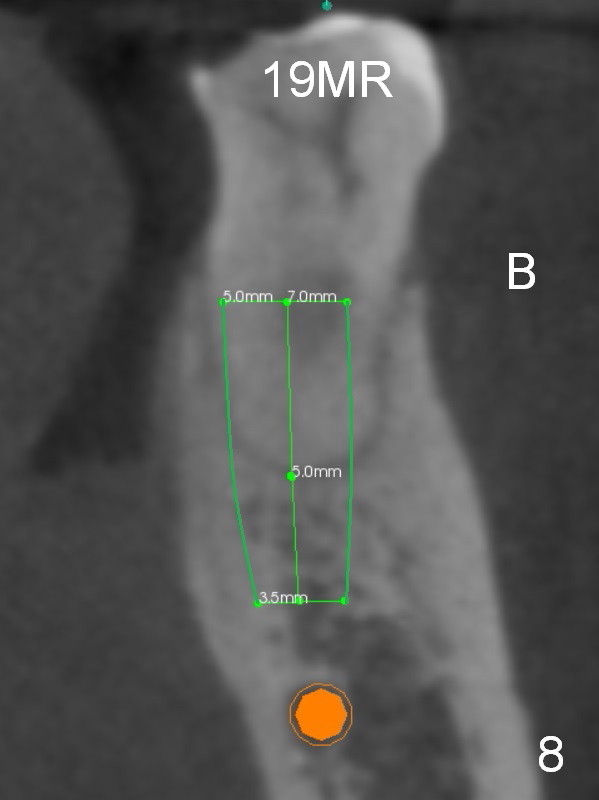

There is severe bone resorption around the distal root of the lower left 1st molar of the 56-year-old man (WG), while the loss of the 2nd molar is associated with limited bone height (Fig.1). A 5x14 mm implant will be placed at the mesial socket of #19 and 5.9 or 6.4x6 mm one is at the mesial site of #18 (Fig.7-9). Use a 2 mm pilot drill with 6 mm stopper from Sinus Master Kit (with extension) to initiate osteotomy at #18 immediately distal to the crown of #19, parallel to the long axis of the latter (Fig.2). After inserting a parallel pin at #18, extract the tooth #19 (Fig.3, antibiotic pending) and start osteotomy with a 2 mm pilot drill with 14 mm stopper (Fig.4). Insert the calibrated parallel pin at #19 (Fig.5) and measure the distance between the two parallel pins (approximately 10 mm, Fig.7). Sequential osteotomy and application of the Tatum taps (Fig.6 red rectangle) will push the septum distal (green arrow). As to #18 osteotomy, trephine, final and tap drills are to be used with control of the depth: 6 mm (Fig.7,9).